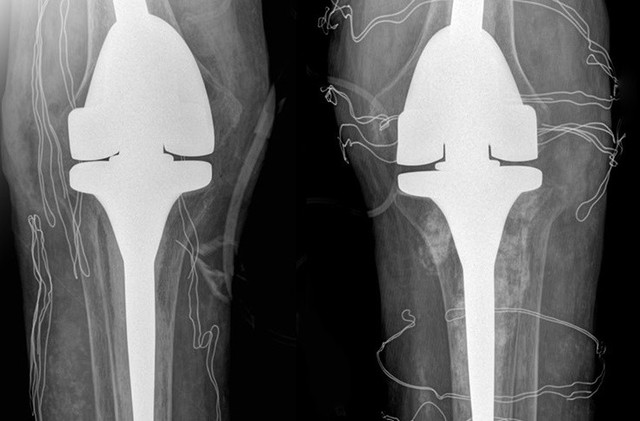

Phim chụp X-quang hai bên khớp gối nhân tạo của bệnh nhân. Ảnh: Bệnh viện Đa khoa Tâm Anh.

ThS.BS Nguyễn Quang Tôn Quyền, Phó khoa Chấn thương Chỉnh hình, Bệnh viện Đa khoa Tâm Anh Hà Nội chẩn đoán, bệnh nhân mất khả năng duỗi khớp gối, chỉ co được 60-70 độ, chụp X-quang cho thấy hai khớp gối bệnh nhân biến dạng nặng, tổn thương tophi khiến khớp và xương tiêu. Kiểm tra loại “thuốc” mua trên mạng mà anh T. uống, bác sĩ phát hiện là sản phẩm hỗ trợ sức khỏe đã bị Cục Quản lý Thực phẩm và Dược phẩm Mỹ (FDA) cảnh báo chứa chất dexamethasone gây nguy hiểm.

Nam bệnh nhân được chỉ định phẫu thuật thay khớp nhân tạo. Xét nghiệm máu trước mổ cho thấy nồng độ cortisol và ACTH (hormone kích thích tuyến thượng thận sản xuất cortisol) thấp. Bác sĩ Quyền chẩn đoán bệnh nhân bị suy tuyến thượng thận do lạm dụng chất dexamethasone dài ngày.

Ê-kíp bác sĩ loại bỏ các hạt tophi gây cản trở vận động, thay thế khớp gối đã tổn thương bằng loại khớp nhân tạo có bản lề, dành riêng cho bệnh nhân có các biến dạng khớp nghiêm trọng. Hậu phẫu, bệnh nhân tiếp tục truyền thuốc ổn định nồng độ hormone tuyến thượng thận trong 2 ngày, sau đó duy trì uống thuốc hormone thay thế.